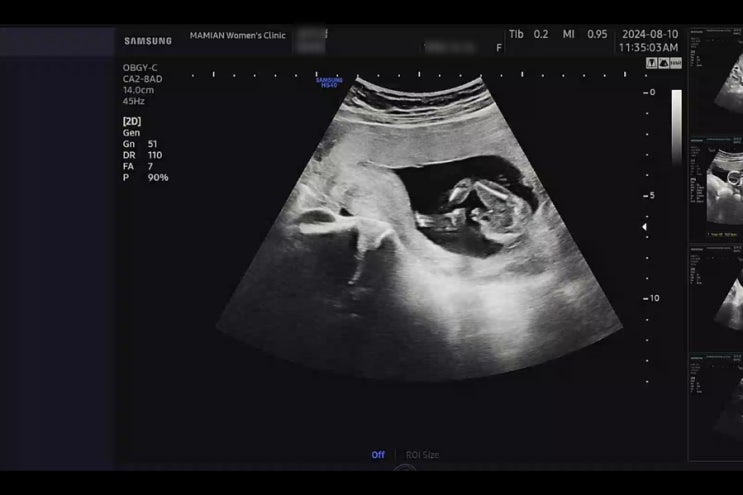

[임신 기록 : 둘째] 19주 23주 임신 기록. 파티마 여성 병원 임당 검사. 정밀 초음파.

오랜만에 쓰는 19주 차, 23주 차 둘째 임신 기록! 장꼬맹을 출산했던 병원은 이제 분만을 안 한다고,, 분만...